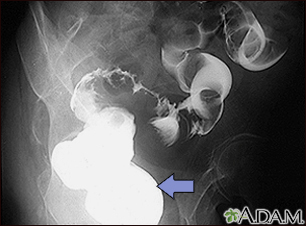

Sigmoid colon cancer - x-ray